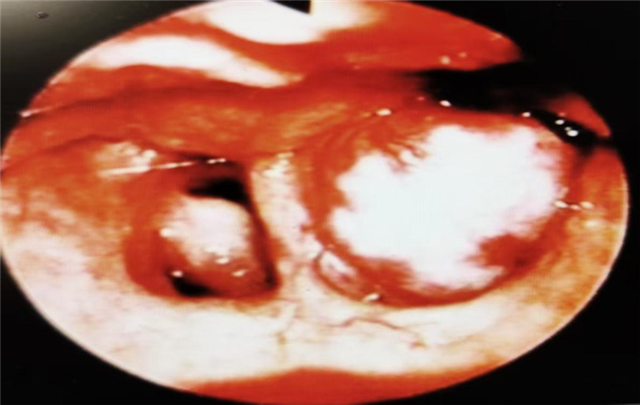

图片1:鼻咽镜下左侧鼻咽顶鼻咽纤维血管瘤表现(图片来源于百度)